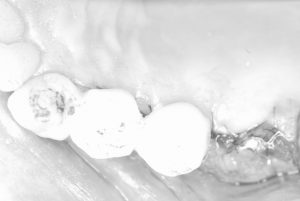

同時4本インプラント埋入オペです

成熟埋入2本/ソケットリフト1本/暫間インプラント1本

歯槽骨質はタイプD4、、かなり柔らかくボソボソした状態の骨の為、全てにデンサーバーを使用し骨質改善の緻密化を計りました!

密着値のISQ値も全て70後半値

即時に仮歯も装着し終了!(画像は全て患者さんの同意を得ています)